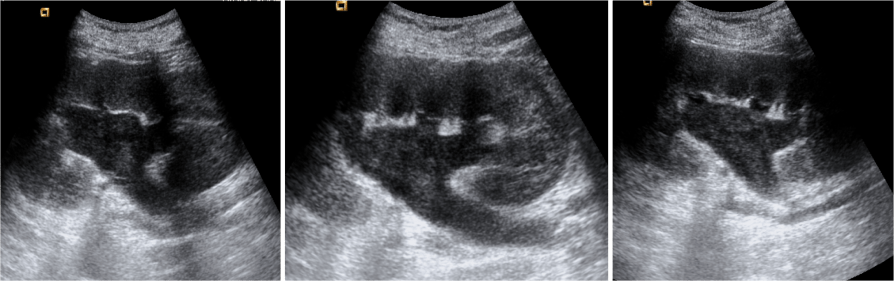

Ecografía:

- Debris ecogénicos en el interior del sistema colector: es es signos más fiable para diagnosticar una pionefrosis (S 90%, E 97%).

- Dilatación del sistema pielocalicial.

- Niveles líquido-líquido en el sistema colector.

- A veces pueden verse ecos sucios correspondientes a gas.

- Engrosamiento de la pared de la pelvis (>2mm).